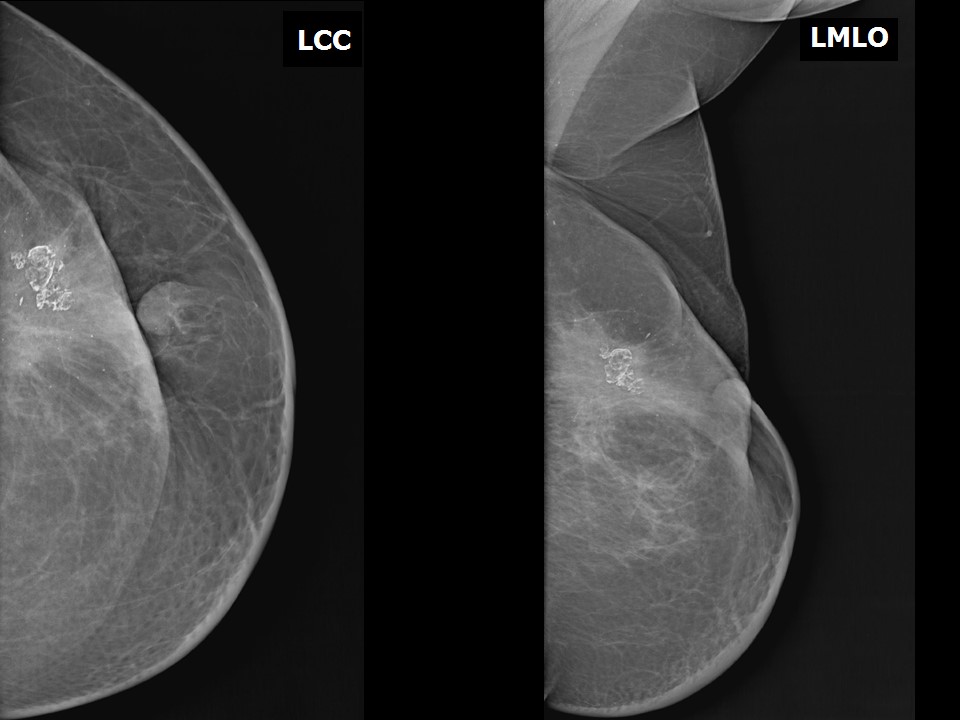

From screening.iarc.fr

Atlas of breast cancer early detection What Do Calcium Deposits In Breast Mean In some instances, certain types of. Breast calcifications are calcium deposits within breast tissue. Breast calcifications are small pieces of calcium deposited into breast tissue and are very common. Breast calcifications are small calcium deposits that develop in a woman's breast tissue. Breast calcifications are calcium deposits that are found in breast tissue and are fairly common, especially in women. What Do Calcium Deposits In Breast Mean.

From www.ajronline.org

Breast Calcifications The Focal Group AJR What Do Calcium Deposits In Breast Mean Called calcifications, these deposits can appear as bright white specks in mammograms. Often not cancerous, breast calcifications are detected on mammograms. Breast calcifications are small calcium deposits that develop in a woman's breast tissue. They are very common and are usually benign (noncancerous). As breast cells grow and divide, calcium deposits can build up in breast tissue. They appear as. What Do Calcium Deposits In Breast Mean.